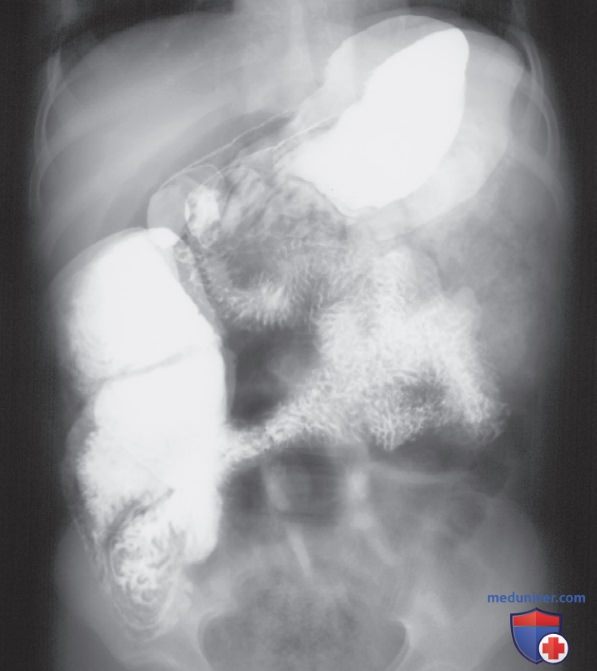

Пространственное разрешение рентгенограммы при оценке ее качества

Рисунок 10. Рентгенограмма, демонстрирующая двойную экспозицию органов брюшной полости в ПЗ проекции. Желудок и кишечник заполнены бариевой взвесью.

5. Двойная экспозиция:

• В компьютерной рентгенографии изображение с двойной экспозицией можно получить при экспонировании двух проекций на одну и ту же кассету ПИ без проведения обработки между экспозициями. Проекции, экспонированные на ПИ, могут быть совершенно разными, и тогда их легко идентифицировать (рис. 9), либо они могут быть одинаковыми, и тогда будут почти идеально совмещаться (рис. 9). Рентгенограмма при двойной экспозиции в одной и той же проекции обычно выглядит размытой, что можно ошибочно объяснить движением пациента (рис. 10). При оценке размытой рентгенограммы следует обратить внимание на кортикальный контур костей, лежащих продольно и поперечно. Если выявляется одинарный контур, это значит, что пациент сместился во время экспозиции, а если визуализируется двойной контур, это значит, что экспозиция выполнялась дважды, и пациент при второй экспозиции находился в несколько ином положении